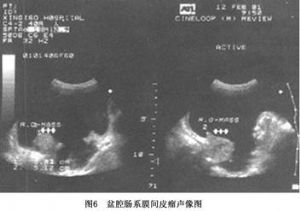

(4)B超:腹部声像特征为腹膜局限性增厚和大量腹水。受累腹膜呈局限性增厚,厚薄不均,腹膜线宽窄不一或中断。早期超声显像最易漏诊或误诊为结核性腹膜炎。病程中晚期病灶增大,形成肿块,呈实质性或混合性回声,轮廓不规则,边界模糊不清(图6)。病变易与邻近肠袢粘连。腹水呈无回声区,一般腹水量较大,粘连的肠袢呈团状回声。肿瘤回声强者应考虑为纤维性间皮瘤,呈混合性或回声相对较低者多考虑为上皮样间皮瘤或混合性间皮瘤。